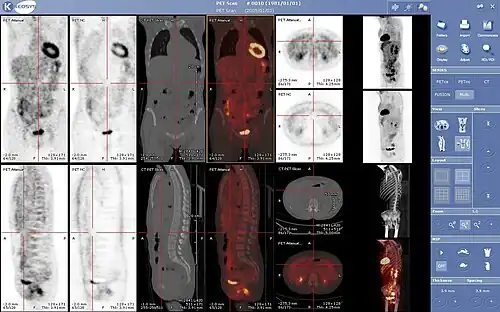

La medicina nuclear es una especialidad de la medicina[1] en la que se utilizan radiotrazadores o radiofármacos (formados por un fármaco transportador y un isótopo radiactivo) para el diagnóstico y tratamiento de enfermedades. Estos radiofármacos se aplican dentro del organismo humano por diversas vías (la más utilizada es la vía intravenosa). Una vez que el radiofármaco está dentro del organismo, se distribuye por diversos órganos dependiendo del tipo empleado. La distribución de este es detectado por un aparato detector de radiación llamado gammacámara y almacenado digitalmente. Luego se procesa la información obteniendo imágenes de todo el cuerpo o del órgano en estudio. Estas imágenes, a diferencia de la mayoría de las obtenidas en radiología, son imágenes funcionales y moleculares, es decir, muestran cómo están funcionando los órganos y tejidos explorados o revelan alteraciones de los mismos a un nivel molecular.

Se utiliza para diagnosticar y determinar la gravedad y tratamiento de una o varias enfermedades, incluyendo cáncer en diversos tipos, enfermedades cardíacas, gastrointestinales, endocrinas, desórdenes neurológicos, y otras anomalías dentro del cuerpo. Debido a que los procedimientos de medicina nuclear pueden detectar actividades moleculares dentro del cuerpo, ofrecen la posibilidad de identificar enfermedades en sus etapas tempranas, así también como las respuestas inmediatas de los pacientes a las intervenciones terapéuticas.

Ejemplos de exploraciones

- Gammagrafía renal: se utiliza para examinar la morfología y función de los riñones con el fin de detectar cualquier anomalía, como infecciones u obstrucción del flujo urinario.

- Gammagrafía de tiroides: se utiliza para evaluar la morfología y función tiroideas, especialmente en el hipertiroidismo.

- Gammagrafía ósea: se utiliza para evaluar enfermedades de los huesos y articulaciones, ya sean de origen tumoral, inflamatorio, degenerativo, traumatológico, metabólico o vascular.

- Gammagrafía con galio-67 (Ga67): se utiliza para diagnosticar enfermedades inflamatorias o infecciosas activas, tumores y abscesos.

- Centellograma Tiroideo con tecnecio-99m (Tc99m): se utiliza para localizar nódulos en la tiroides e identificar el mejor tratamiento (esto lo determina el médico).

- Centellograma Tiroideo con iodo-131 (I131) o Captación tiroidea: se utiliza para descubrir mal funcionamiento de la tiroides, generalmente hipertiroidismo, el cual es tratado con dosis de iodo-131 (menores a 30 mCI).

- Dosis Ablativa de iodo-131: se utiliza para destruir las células cancerosas remanentes después de la extirpación de la tiroides.

- Rastreo Corporal con iodo-131: se utiliza para saber si la dosis ablativa aplicada ha sido efectiva en un 100 %, de lo contrario debe darse una nueva dosis.